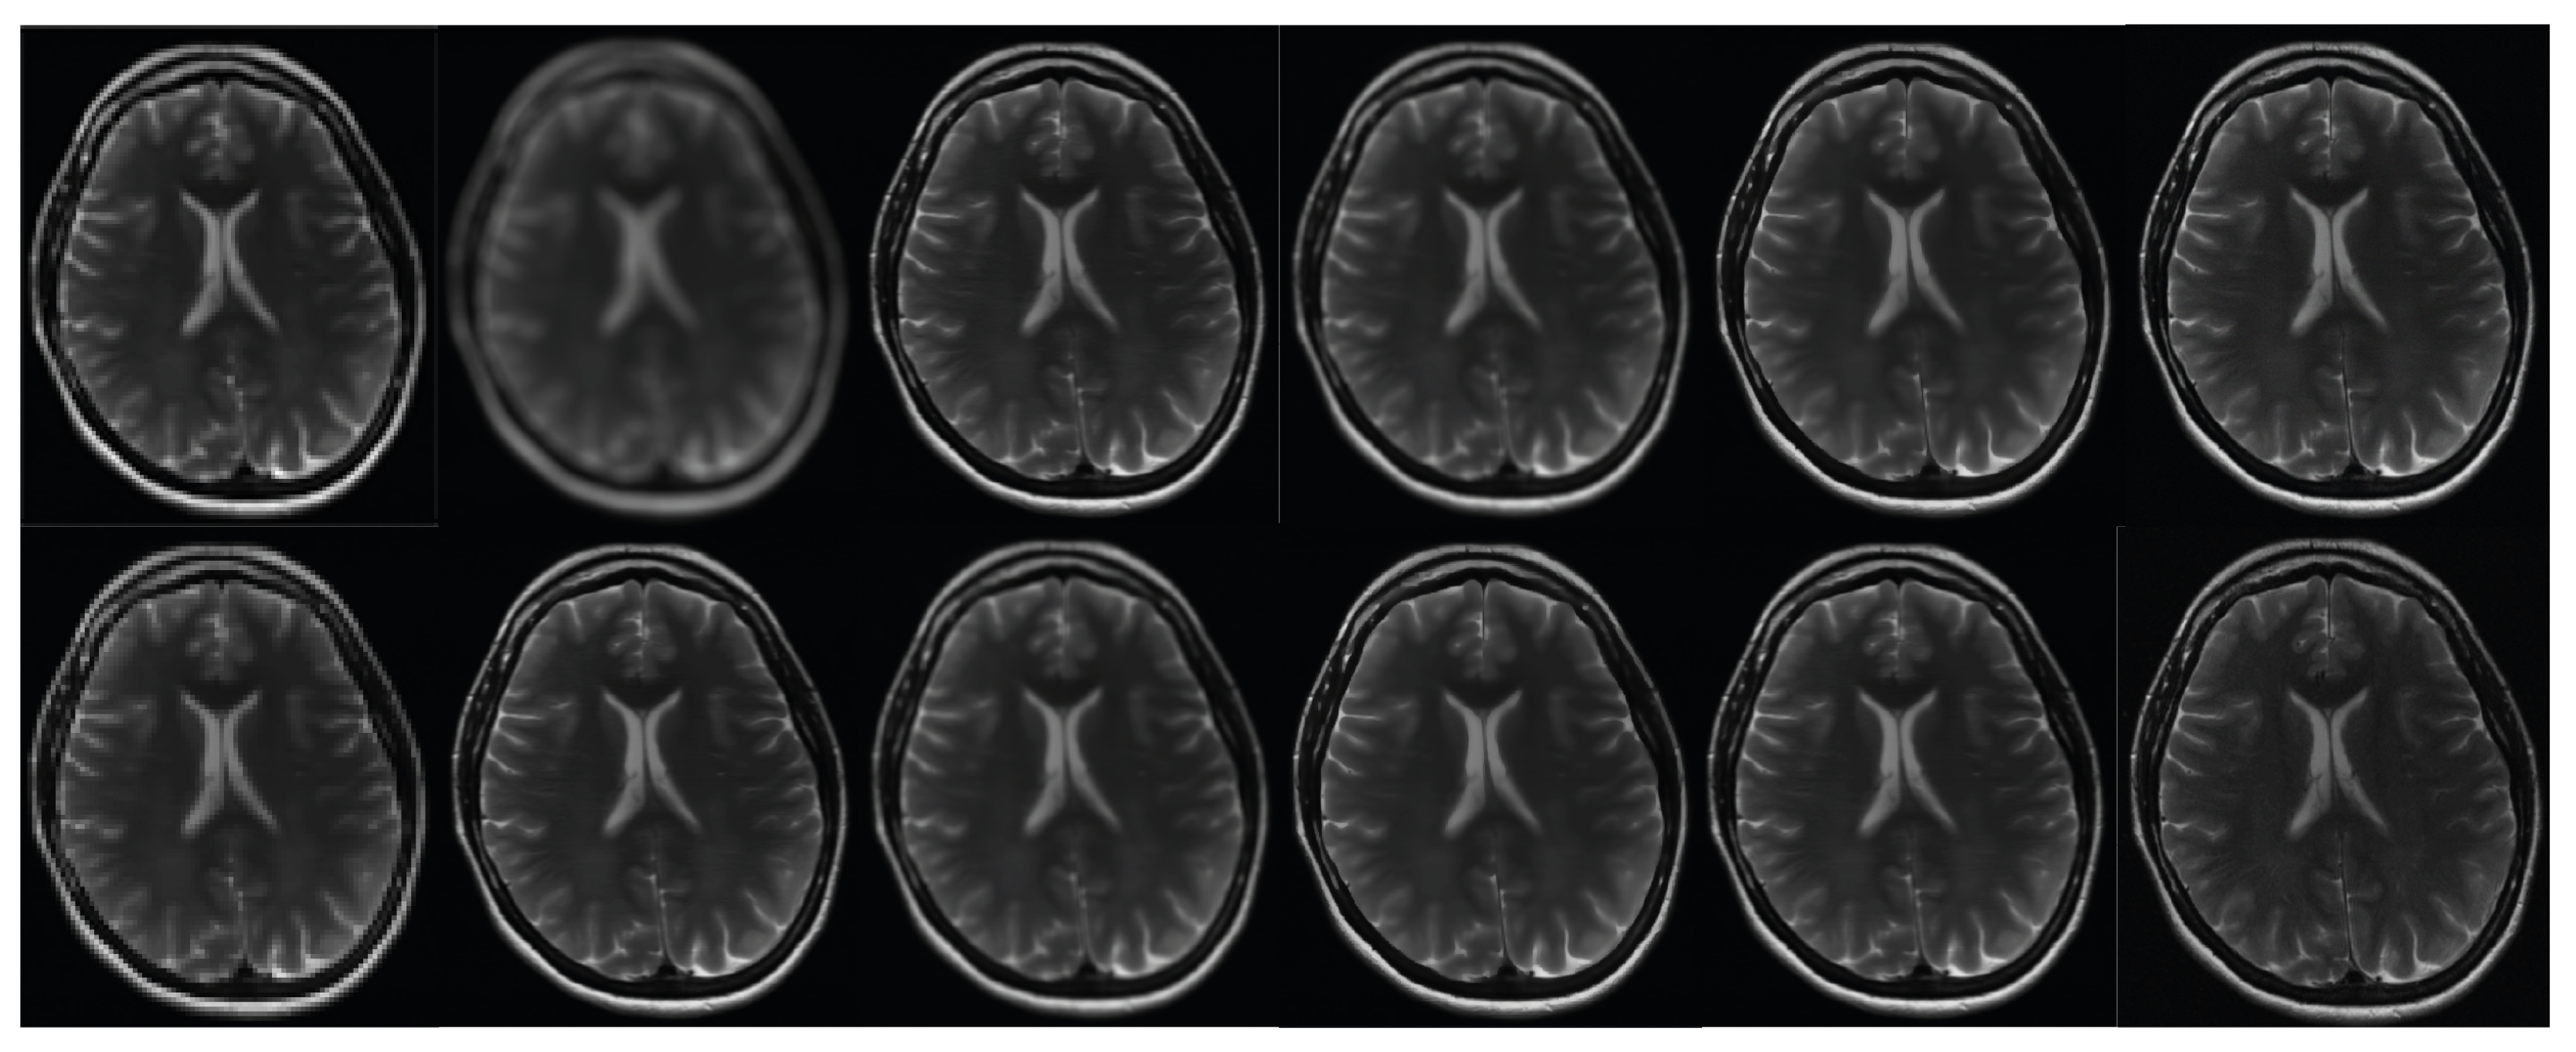

Figure 11. The results of the second phase of the clinical brain imaging trial. This study utilizes the fastMRI test dataset [57]. The current study focuses on the reconstruction of an image using various techniques. In the first row, the regular sampling scheme is utilized without motion correction and with SRR applied (1) (PSNR = 20.11 dB). The reconstruction process involves the use of the B-spline curve (2) (PSNR = 23.31 dB), Yang’s method [50] (3) (PSNR = 27.01 dB), Lim’s method (4) (PSNR = 29.12 dB) as referenced in [20], Zhang’s procedure (5) (PSNR = 28.66 dB) as referenced in [51], and Zhang’s second algorithm (6) (PSNR = 29.71 dB) as referenced in [43]. In the second row, Mahapatra’s method [52] (7) (PSNR = 29.32 dB) and Wang et al.’s [53] procedure (8) (PSNR = 30.62 dB) are employed. Furthermore, the reconstruction procedure utilizes Guerreiro’s approach [54] (9) (PSNR = 28.82 dB), Pham et al.’s method [55] (10) (PSNR = 26.58 dB), Shi’s method [17] (11) (PSNR = 31.22 dB), and the author’s method (12) [20]. Furthermore, in order to achieve super-resolution, a suggested sampling strategy and motion correction techniques are employed. The aforementioned procedures are implemented without the inclusion of supplementary data. The compression ratio is 50%.